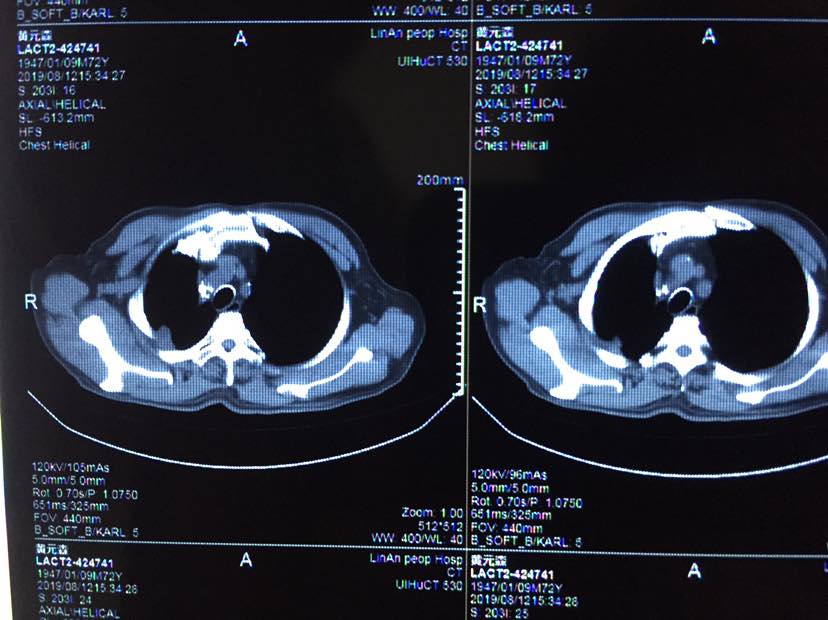

2019年8月9日,父亲接受第十三针k药的治疗,注射之前进行了全面的检查,生化、肿瘤标的物、b超、ct等结果显示,父亲目前状况非常正常,除了肺内胸膜有阴影不能确认活性以外,其他病灶都消失了,父亲现在体感很好,无任何胸痛胸闷气短等症状,依然与常人无异,持续稳定中,希望这种状况能持续的长久一些!也祝各位病友好运长久!